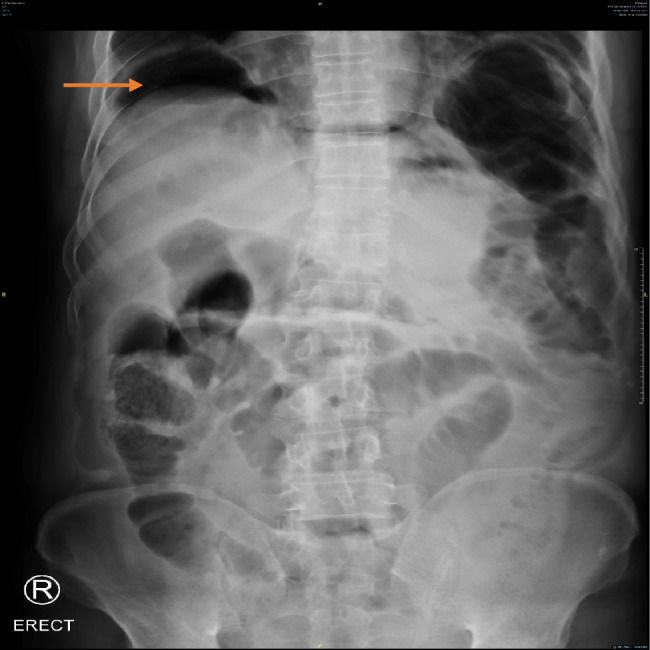

Acute abdomen is a common presentation in the emergency department, requiring prompt evaluation, diagnosis, and treatment. This case report highlights how simple diagnostic tools can facilitate early detection of abdominal pain caused by duodenal perforation-a rare complication in patients with locally advanced pancreatic cancer. We present a novel case of a 62-year-old male with locally advanced pancreatic cancer who developed acute abdominal pain. The diagnosis of intestinal perforation was made at a Specialist Palliative Care clinic within a tertiary cancer centre. An erect abdominal X-ray revealed free air under the diaphragm, pointing to bowel perforation. The patient underwent emergency surgical exploration, which confirmed a duodenal perforation and was managed with a palliative gastrojejunostomy. While point-of-care ultrasound (POCUS) was not used in this case, we emphasize its potential utility as a bedside tool in the emergency setting for early evaluation of acute abdomen. It can aid in differentiating between conditions such as bowel obstruction, perforation, intussusception, abscesses, or large masses compressing vital structures-many of which may not be visible on a plain abdominal X-ray. This case underscores the importance of early clinical evaluation and the use of accessible diagnostic tools (POCUS) in the timely management of acute abdomen, particularly in complex cancer cases.